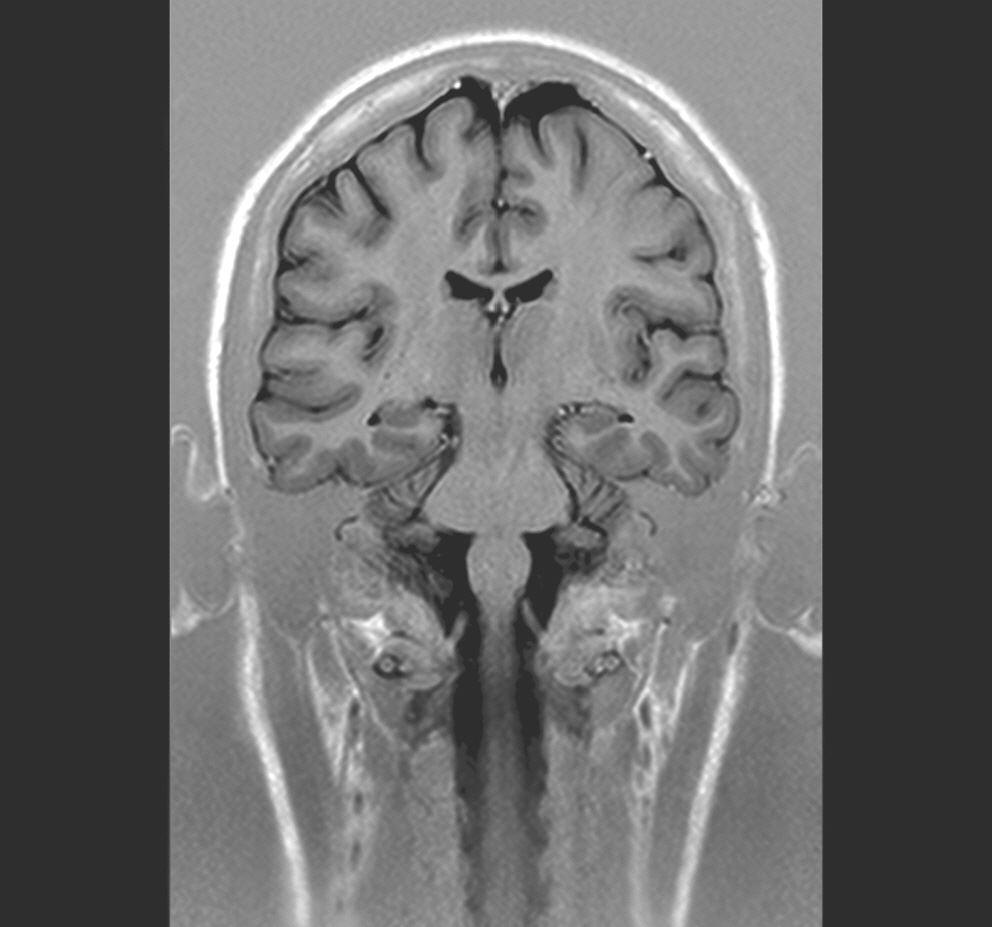

MRT Kopf coronar

Das gilt nicht nur für das Gehirn, sondern auch für den Rückenmarkskanal und das darin verlaufende Rückenmark sowie die Nervenwurzeln.